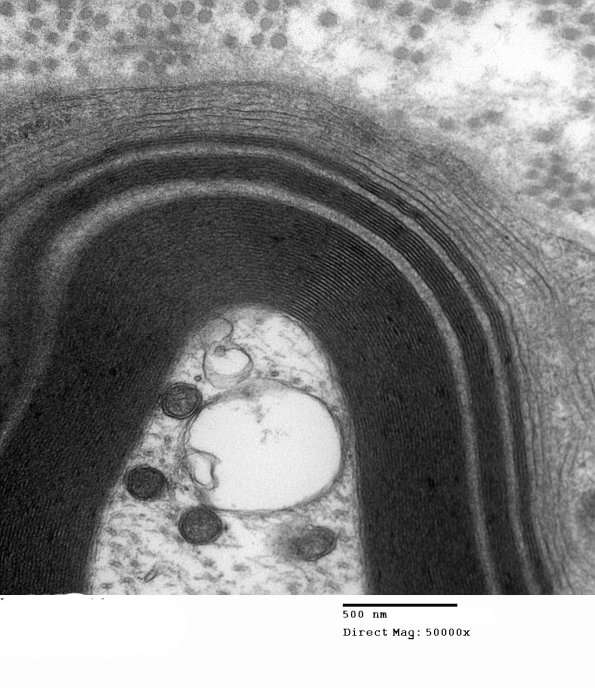

Additional WSM involving this axon. (electron micrograph)